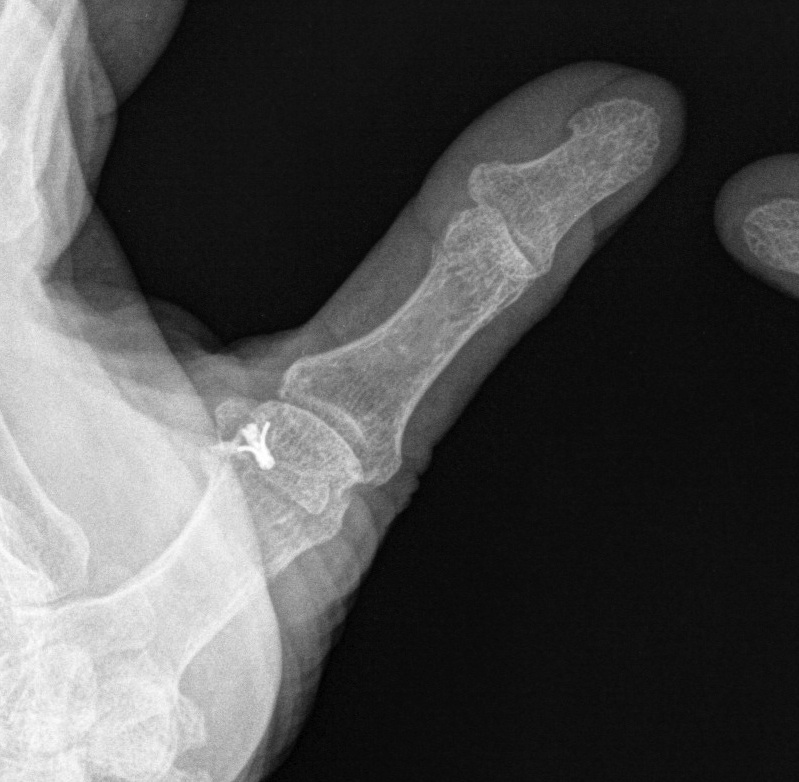

X-ray

3 types Bony avulsion

1. Small fragment pulled away from P1

2. Large intra-articular fracture involving >1/4 articular surface

3. S-H III in paediatric population